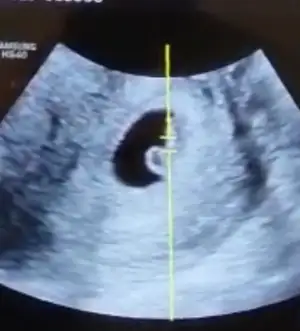

Bebeğimin cinsiyeti

melegim can melegim can ay artık belli olur mu cinsiyeti ya 🤗🤗 karından bakıldı 🙈 ortada gibi sanki ama

Ben de erkek diyorum canım kese şeklinden dolayı, öyle çok bir şey bildiğimden değil de benim oğlanın kesesi de böyle fasülyemsiydi oradan çıkarım yaptım. Sen ne hissediyorsun ve ne istiyorsun 💃